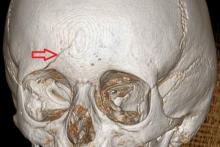

Przypadek 58: 6-latek po urazie głowy okolicy czołowej - zderzenie z kolegą.

Rozpoznanie: w wykonanym badaniu TK głowy - złamanie kości czołowej po stronie prawej. Szczelina złamania obejmuje łuskę kości czołowej (strzałka) oraz górną ścianę oczodołu prawego (nie pokazano na zdjęciach). Bez zmian pourazowych śródczaszkowo.